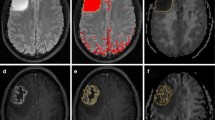

Meta-analysis of diagnostic test accuracy

For diagnostic test accuracy (DTA) of DKI in differentiating HGGs from LGGs, 9 of the 12 selected studies were eligible for a bivariate random-effect meta-analysis [20,21,22,23,24,25, 29,30,31]. The pooled sensitivity was 0.87 (95% CI 0.78–0.92) and specificity was 0.85 (95% CI 0.76–0.91). Forest plots of sensitivity and specificity of studies are shown in Figs. 4 and 5, respectively. The summary receiver operating characteristic (ROC) curve is shown in Fig. 6 with an area under the curve (AUC) of 0.92. DTA analysis revealed that the DKI false-positive rate was 0.15 (95% CI 0.09–0.24). Bivariate meta-regression model showed study level characteristics such as TE, TR, max b value, no. of b values and number of diffusion direction had no significant effect on diagnostic accuracy (p = 0.155 to p = 0.893).

To date, there have been only two published meta-analyses which have looked at the diagnostic test accuracy (DTA) of DKI in glioma discrimination and both demonstrated very promising initial results [10, 11]. Our systematic review and meta-analysis extend this further by increasing the number of electronic databases, removing language restrictions and broadening the eligibility criteria. Importantly regarding DTA of DKI in addition to studies, which follow the WHO 2007 classification, we also included studies using the current WHO 2016 classification, the latter the IDH genotype. Our systematic review included a total of 19 studies, and for looking at the role of DKI in glioma stratification, two meta-analyses were performed. For mean difference analysis of mean kurtosis (MK) across 12 studies, we demonstrated a statistically significant mean difference in MK between high-grade gliomas and low-grade gliomas of 0.22 (95% CI 0.19–0.25). These results are comparable with the Delgado et al., where across 10 studies, they found a significant MK mean difference between high- and low-grade gliomas of 0.17 (95% CI 0.11–0.22) [10]. Our second meta-analysis included 9 studies, assessing the overall diagnostic test accuracy of DKI in grading gliomas, further confirmed its high diagnostic potential with an 87% sensitivity, 85% specificity and 0.92 pooled area under the curve. This is similar to the Delgado group findings which were across a smaller group of 5 studies, which produced a pooled sensitivity and specificity of 85% and 92% respectively and a pooled area under the curve of 0.94.

For the second question, looking at the role of DKI in differentiating glioma from non-gliomatous CNS tumours, our literature search only identified two studies which did not allow us to obtain any conclusive results [18, 19]. These studies showed however encouraging results that need to be reproduced in the future. Yan Tan et al. analysed MK values in solid tumour parts and the periphery of high-grade astrocytomas (HGAs) and solitary metastatic lesions, concluding that MK values differed significantly in the periphery between the two entities. MK values were also more sensitive than diffusion tensor imaging (DTI) metrics [19]. Using DKI, Pang et al. aimed to differentiate between HGGs and primary CNS lymphomas (PCNSLs) [18]. They reported significantly higher MK in PCNSLs than HGG, which could perhaps be explained by the hypercellular nature of lymphomas microenvironment.